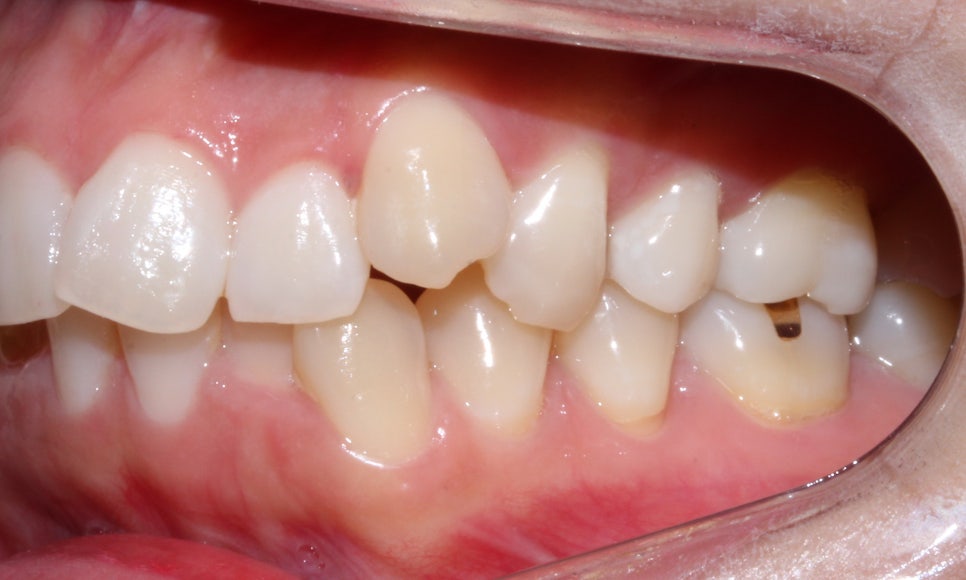

돌출입, 덧니교정 후 사진

돌출입, 덧니치아 2D교정으로 완성! by.투디치과(2D치과)

<14개월 교정이 끝난 후 모습>

교정이 끝난 모습입니다:-D

덧니교정일 경우에는 치아가 배열되면

겹쳐져 있던 치아가 제자리로 돌아오면서

블랙트라이앵글 (black triangle)이

생길 가능성이 높습니다.

이런 경우에는 사전에 상담을 통해

가능성을 공지받고 어떠한 방식으로

치료를 진행할 것인지 환자분과

상의 후 교정이 진행됩니다.